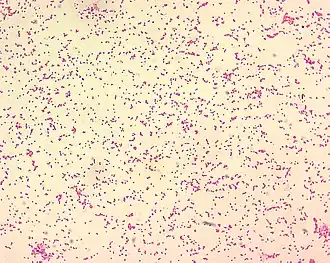

Células de Brucella spp. | ||

Brucellaceae es una familia de bacterias gram-negativas del orden de las Rhizobiales. Son de pequeño tamaño y su forma va desde cocoides a esferas. Son parásitos obligados o facultativos, fundamentalmente de vertebrados de sangre caliente e incluyen a serios patógenos como Brucella , intracelulares de mamíferos. El género Brucella incluye diversas especies bacterianas que ocasionan en el hombre y en los animales el conjunto de enfermedades conocidas como brucelosis.